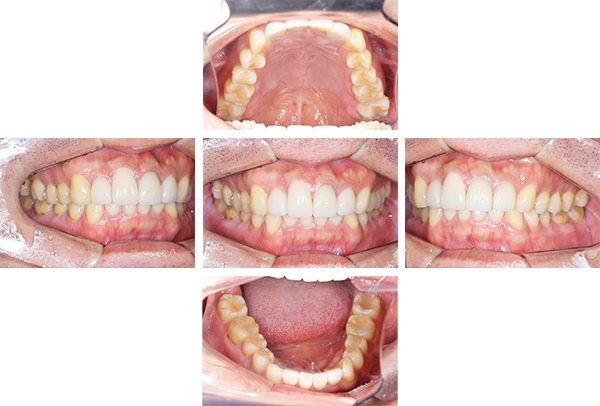

歯列矯正・インレー・クラウン症例

前歯が黒っぽいのが気になる、

悪いところは全部治したい

年齢 54代女性

主訴 歯をきれいにしたい

治療

期間

4年

費用 セラミックインレー 12本

660,000円

オールセラミックプレミアムクラウン 3本

495,000円

矯正 874,900円

計 2,029,900円(税込)

症例写真(治療前)

治療前:

八重歯が目立ちます。また銀歯もおおく、見た目が気になります。虫歯も散見できます。